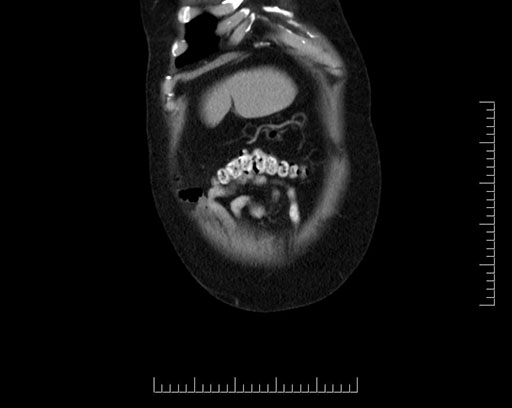

Imaging Analysis

Look through the patient's CT scan to identify any areas of concern for the necessary procedure.

Based on your CT findings, which issue(s) would give reason for "planned slowing down moment(s)" in this case?